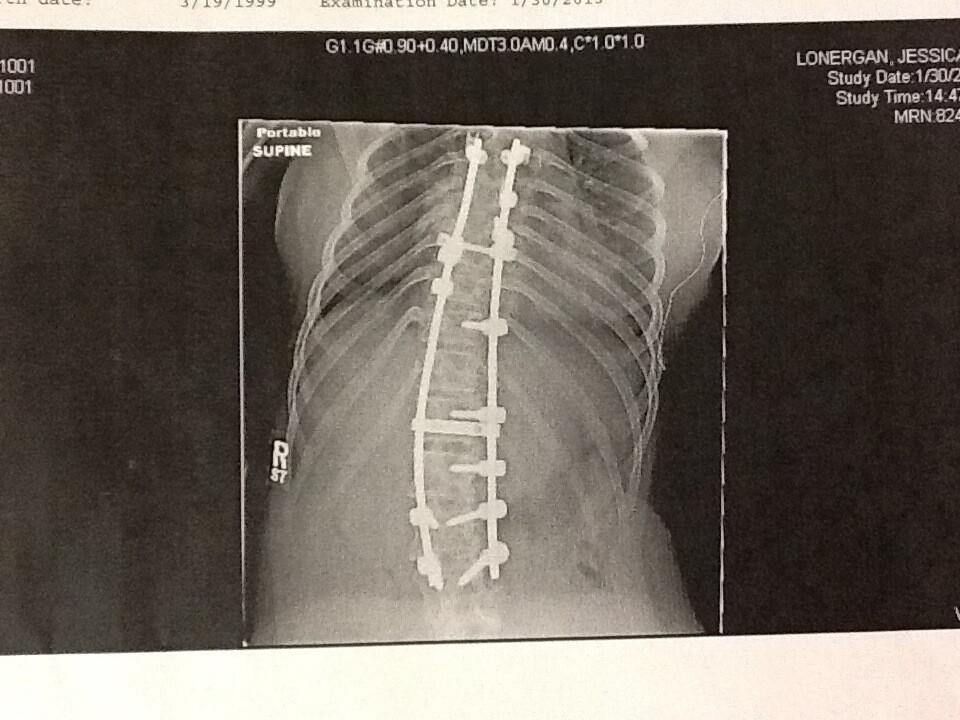

Suốt thời thơ ấu và niên thiếu, Jessica ở viện nhiều hơn ở nhà. Cô đã trải qua 2 cuộc phẫu thuật não và nhiều phác đồ điều trị phức tạp để đặt 4 thanh cố định và 28 ốc vít ở lưng. Bất chấp đau đớn và chiếc nẹp lớn ở lưng, Jessica vẫn kiên trì tập đi từ năm 6 tuổi.

| Ảnh điều trị cột sống của Jessica |